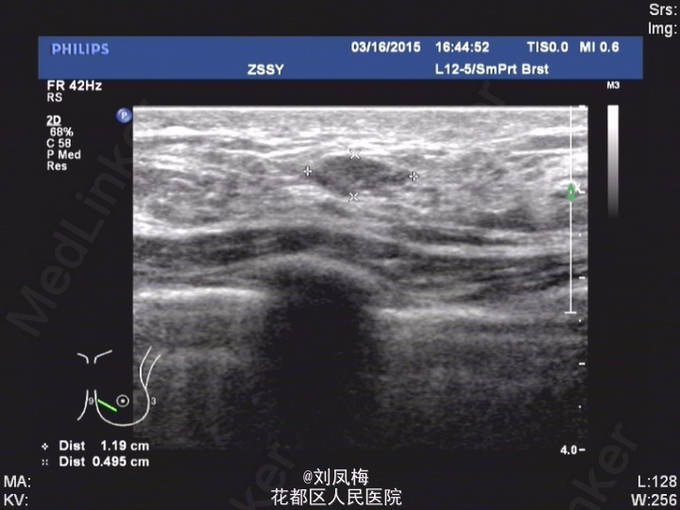

查体:神清,双乳不对称,右乳较左乳稍增大并下垂,右乳9点钟方向可扪及多发结节,较大者约2cm,形态不规则,质中,边界不清楚,按压无疼痛,活动度可。左侧乳房未扪及明显肿物。挤压双侧乳头无液体流出。双侧腋窝未及明显肿大淋巴结。 乳腺B超:双侧乳腺多发实性肿物,BI-RADS 3类(乳腺纤维瘤?)。 双侧乳腺小叶增生声像。 双侧腋窝未见明显异常肿大淋巴结

入院完善相关检查,排除手术禁忌证后于2015-3-17在局麻下行右乳肿物真空旋切术。 术后病理诊断:(右乳肿物)纤维腺病伴腺瘤样结构形成。